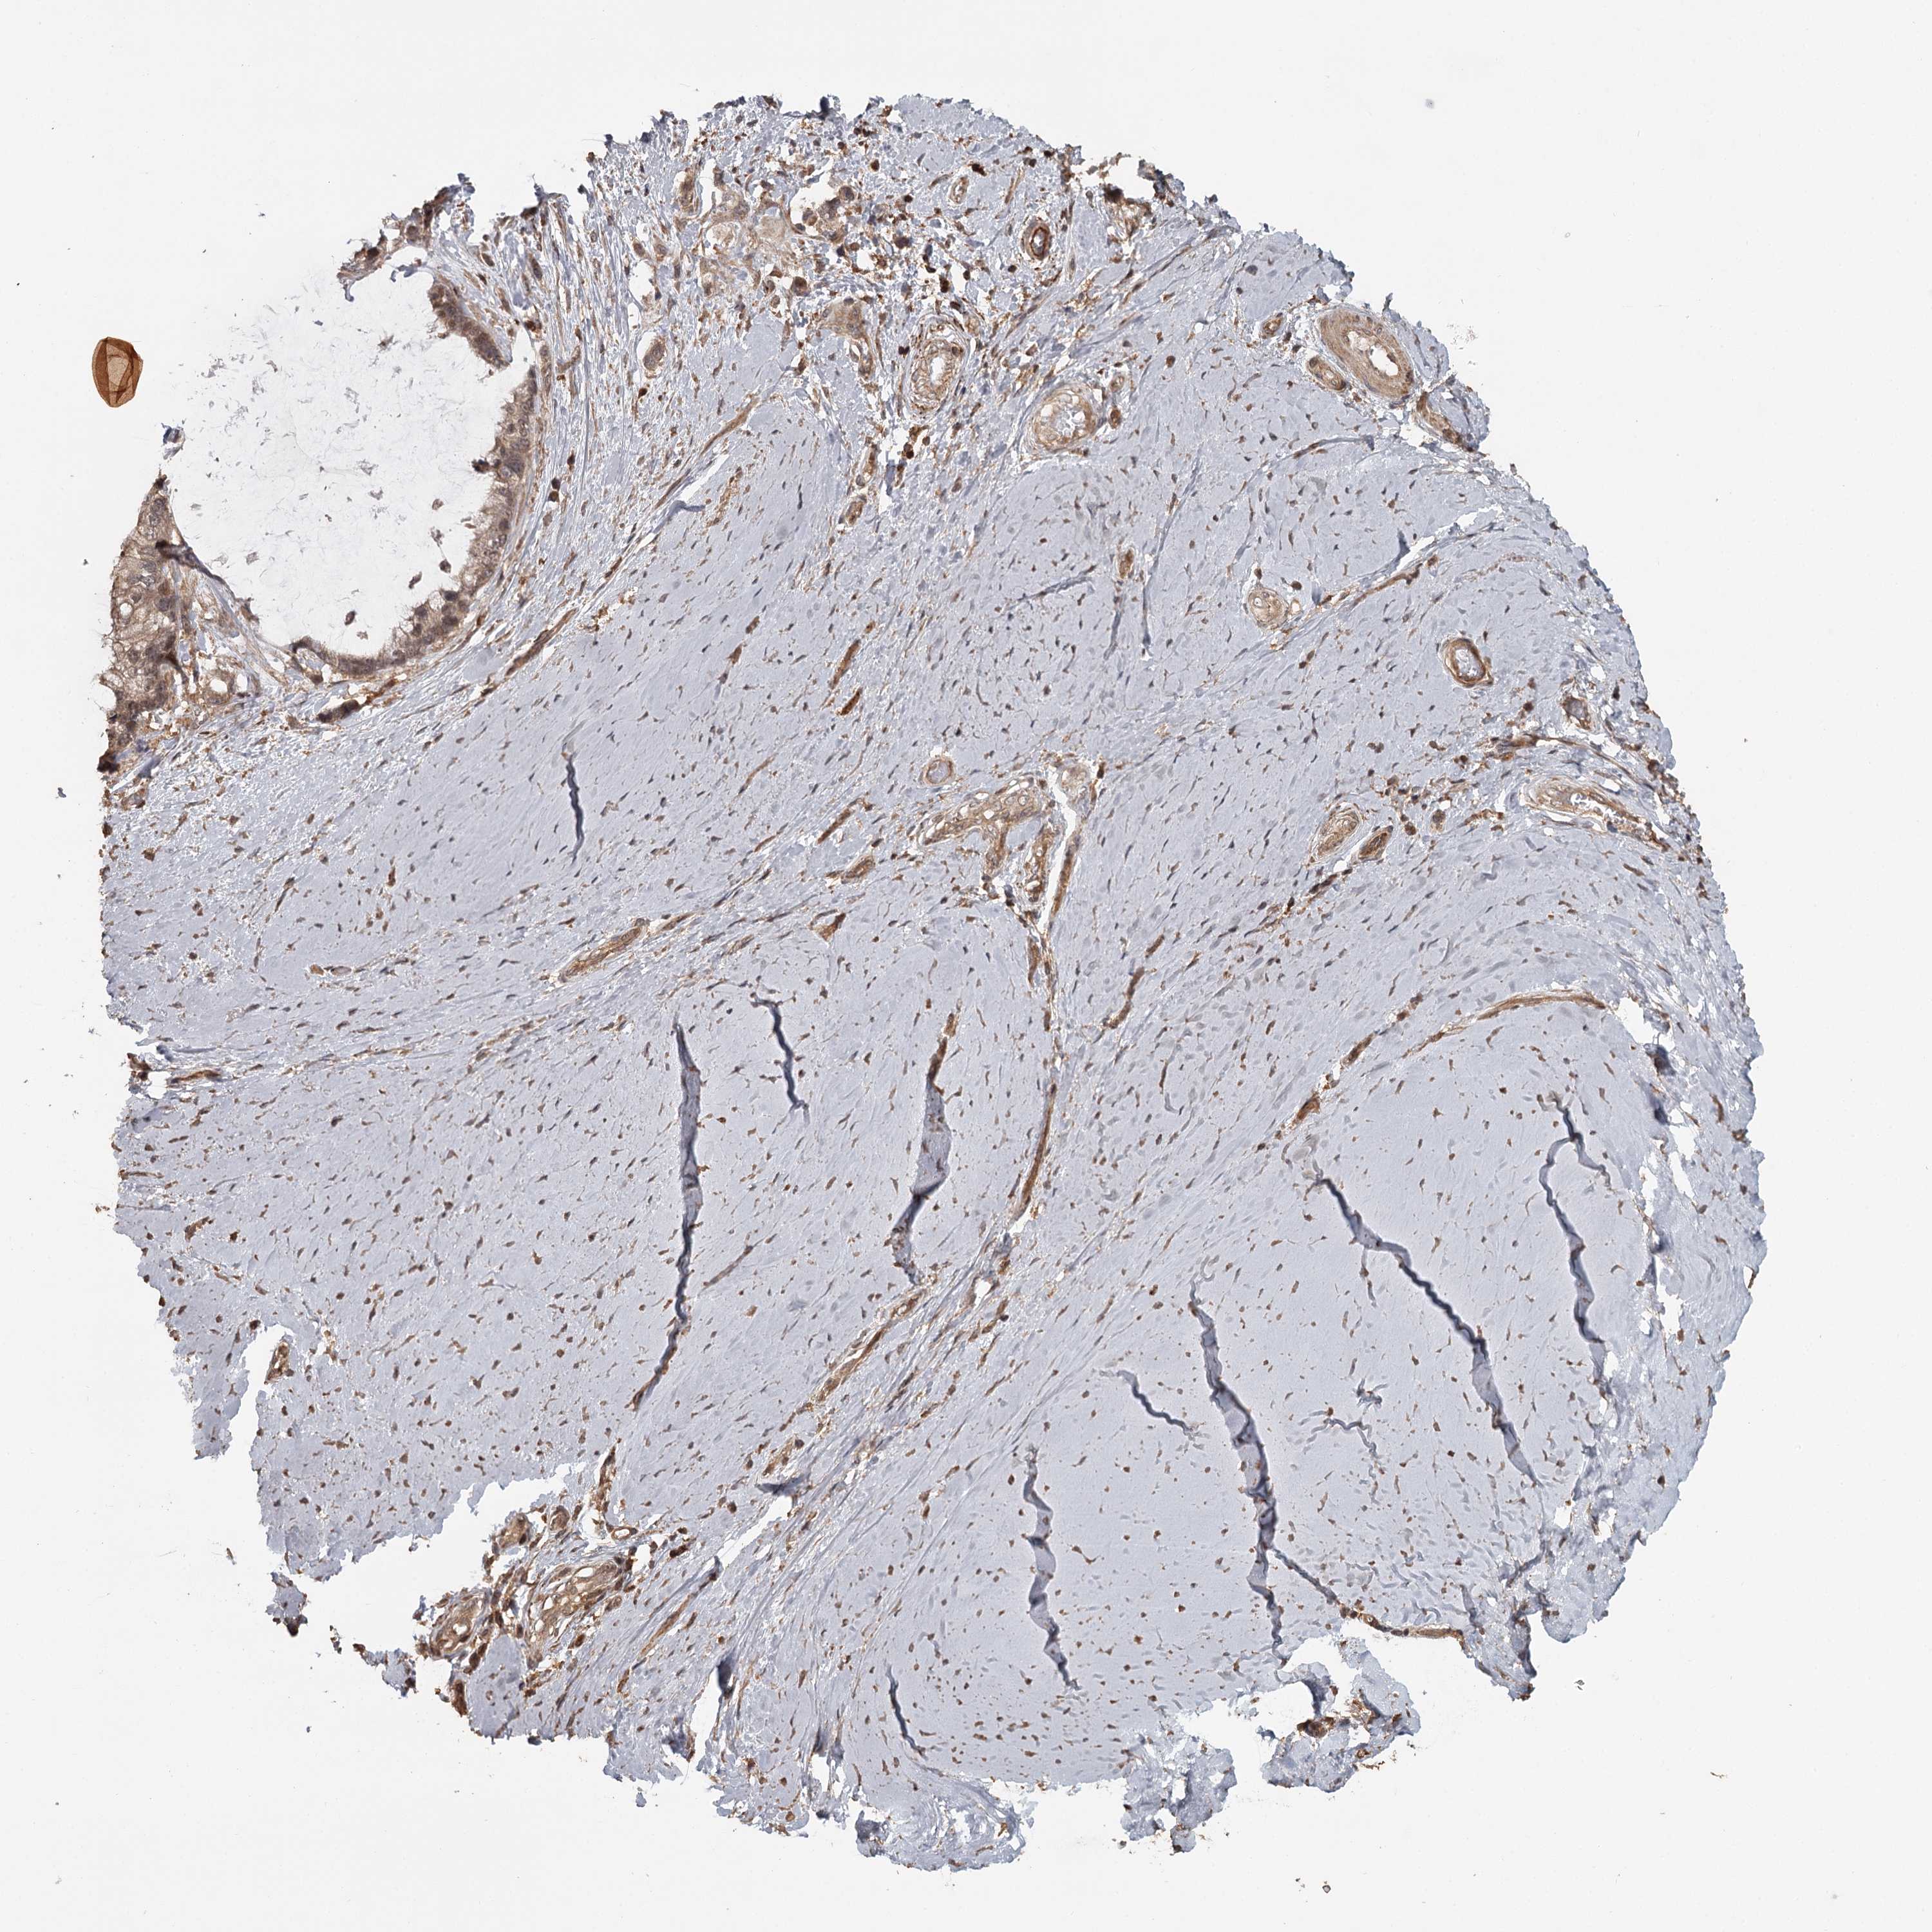

OVARIAN CANCER - Protein expressioni

A mouse-over function shows sample information and annotation data. Click on an image to view it in a full screen mode. Samples can be filtered based on level of antibody staining by selecting one or several of the following categories: high, medium, low and not detected. The assay and annotation is described here.

Note that samples used for immunohistochemistry by the Human Protein Atlas do not correspond to samples in the TCGA dataset.

Antibody stainingi

Antibody staining in the annotated cell types in the current human tissue is reported as not detected, low, medium, or high, based on conventional immunohistochemistry profiling in selected tissues. This score is based on the combination of the staining intensity and fraction of stained cells.

Each image is clickable and will lead to virtual microscopy that enables deeper exploration of all samples and also displays staining intensity scores, fraction scores and subcellular localization as well as patient and tissue information for each sample.

Antibody HPA039106

Staining

High

Medium

Low

Not detected

Intensity

Strong

Moderate

Weak

Negative

Quantity

>75%

75%-25%

<25%

None

Location

Nuclear

Cytoplasmic/membranous

Cytoplasmic/membranous,nuclear

Cystadenocarcinoma, serous, NOS

Carcinoma, endometroid

Cystadenocarcinoma, mucinous, NOS

Carcinoma, NOS